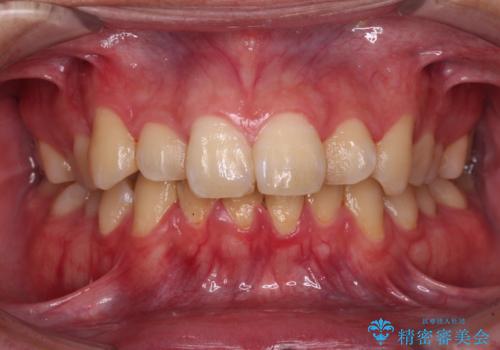

八重歯を矯正治療で治したい!